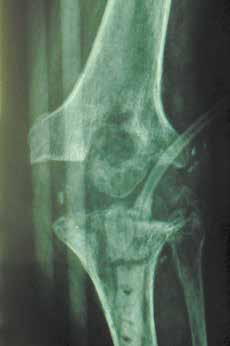

Der endoprothetische Ersatz des Kniegelenks stellt ein gebräuchliches und meist auch komplikationsfreies Verfahren bei arthrotischen Veränderungen des Kniegelenks dar. Bisweilen kommt es aber zu chronisch rezidivierenden Infekten der Implantate, die allen konservativen und operativen Maßnahmen zum Trotz erst zum Stillstand kommen, wenn das Kunstgelenk ein für alle Mal entfernt wird. Die Osteomyelitis führt zur Lockerung der Prothese und sekundär zur Osteoporose, zu Weichteil- und Knochennekrosen und spontanen Frakturen (Abb. 1a–c). Die septische Chirurgie stellt ungewohnte Anforderungen an den Mediziner. Verspätete Diagnostik und eine insuffiziente Therapie verschlimmern die Situation oft zusätzlich. Leider werden die möglichen Komplikationen häufig totgeschwiegen. So werden sie weder in dem 2013 erschienenen Buch über „Infektionen des Bewegungsapparates“ 1 noch im Übersichtsbeitrag in der Swiss Medical Weekly von Ahmad et al. 2 erwähnt. Hingegen berichtet Greitemann aus Bad Rothenfelde, in seiner Rehabilitationsklinik Münsterland habe er seit 1995 38 solcher Patienten mit Amputationen aufgenommen 3.